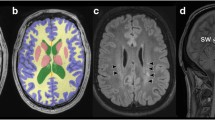

The accurate and precise measurement of brain volumes in young children is important for early identification of children with reduced brain volumes and an increased risk for neurodevelopmental impairment. Brain volumes can be measured from cerebral MRI (cMRI), but most neuroimaging tools used for cerebral segmentation and volumetry were developed for use in adults and have not been validated in infants or young children. Here, we investigate the feasibility and accuracy of three automated software methods (i.e., SPM, FSL, and FreeSurfer) for brain volumetry in young children and compare the measures with corresponding volumes obtained using the Cavalieri method of modern design stereology.

Cerebral MRI data were collected from 21 children with a complex congenital heart disease (CHD) before Fontan procedure, at a median age of 27 months (range 20.9–42.4 months). Data were segmented with SPM, FSL, and FreeSurfer, and total intracranial volume (ICV) and total brain volume (TBV) were compared with corresponding measures obtained using the Cavalieri method.

Agreement between the estimated brain volumes (ICV and TBV) relative to the gold standard stereological volumes was strongest for FreeSurfer (p < 0.001) and moderate for SPM segment (ICV p = 0.05; TBV p = 0.006). No significant association was evident between ICV and TBV obtained using SPM NewSegment and FSL FAST and the corresponding stereological volumes.

FreeSurfer provides an accurate method for measuring brain volumes in young children, even in the presence of structural brain abnormalities.